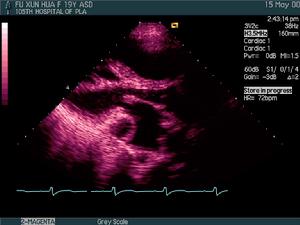

(4)超聲心動圖可見三尖瓣下移及下移程度。注意三尖瓣返流量、前瓣發育情況,有無房缺或卵圓孔未閉。

(3)切面超聲心動圖和都卜勒檢查顯示三尖瓣前瓣葉增大,活動幅度大。隔瓣葉和後瓣葉明顯下移,發育不良,活動度差。三尖瓣關閉延遲,瓣膜位置左移,室間隔動作反常。右心房及房化右心室共同顯示巨大的右心房腔,功能性右心室腔縱徑縮短。都卜勒檢查可顯示心房水平右向左分流和三尖瓣返流。